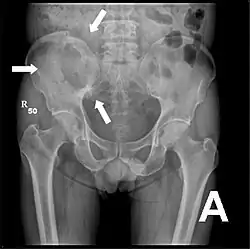

Röntgenaufnahme des Beckens eines Patienten mit Prostatakarzinom: Multiple osteoplastische Knochenmetastasen, insbesondere im Kreuzbein, aber auch im Darmbein, vor allem links (also rechts im Bild), am Sitzbeinhöcker links und im proximalen Oberschenkelknochen links. Nebenbefundlich zeigt sich eine Hüftgelenksarthrose rechts (also links im Bild). -